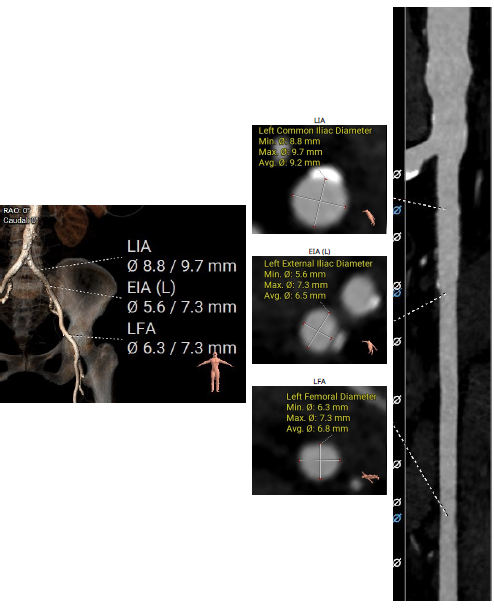

2023年2月10日,重庆医科大学附属第二医院殷跃辉、苏立教授团队联合医院麻醉、超声、放射等多学科团队,成功应用Evolut PRO TAVR系统治疗一名主动脉瓣中度狭窄伴重度关闭不全患者。该病例瓣叶单边增厚,中度主狭伴重度反流,且冠状动脉粥样硬化,阻塞风险高;术者认为介入瓣膜的多次稳定回收性,对手术的成功起至关重要的作用。

患者为76岁女性,因“反复喘累半月”入院。心脏彩超显示,左房、左室增大,升主动脉增宽,肺动脉增宽。收缩期主动脉瓣口流速350cm/s,平均压差:27mmHg,最大压差49mmHg,舒张期主动脉瓣口左室侧见大量红色为主的花色血流信号,速度438cm/s;EF 48%。诊断主动脉瓣中度狭窄伴重度关闭不全、左房、左室增大、心包积液(少量)、左室收缩功能降低、二尖瓣重度关闭不全、三尖瓣轻度关闭不全。既往患有高血压。